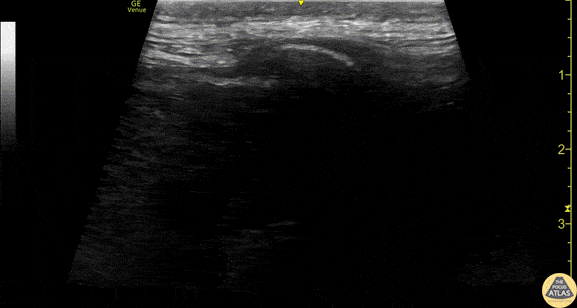

Nerve Block Gallery - Erector Spinae Anatomy Scan

Dynamic view of the anatomy of the erector spinae block. This view is obtained using the linear transducer in a sagittal orientation. The clip starts in the midline, and a pinpoint hyperechoic thoracic spinous process is briefly seen. As the probe is swept laterally, broad hyperechoic transverse processes are seen, with the erector spinae muscles just superficial to these. Further laterally, the transverse processes disappear and broad hyperechoic ribs come into view, with sliding pleura visible underneath. Notice the lack of visible pleura when transverse processes are in view. The erector spinae block is performed in the plane viewing transverse processes, without ribs/pleura visible. Drs. Sam Paskin-Flerlage, PGY4 and Michael Heffler, PGY3 Denver Health Residency in Emergency Medicine